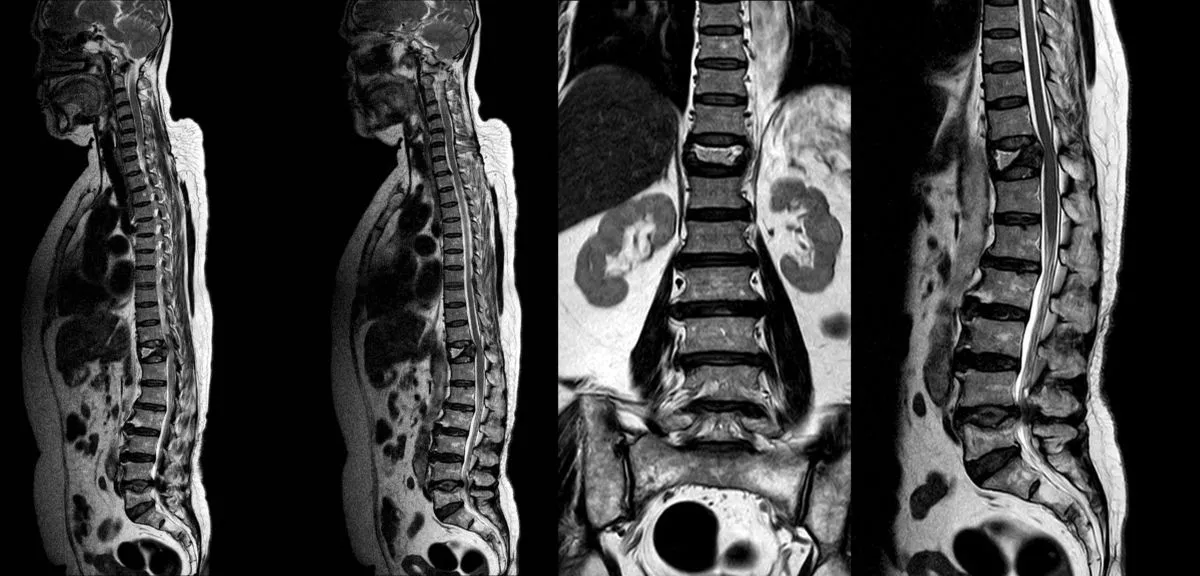

Research from multiple studies confirms that women, despite having fewer traditional risk factors for disc degeneration than men, actually experience more severe disc degeneration. This has been hypothesized to be due to estrogen deficiency-induced vertebral endplate degeneration and impaired nutrient diffusion to the discs. In fact, in a cohort study of over 1,500 women and 1,300 men, women had significantly higher MRI markers of intervertebral disc degeneration, and in postmenopausal women, the number of years since menopause was highly positively correlated with radiographic signs of lumbar disc degeneration.4

Too often, patients receive diagnoses based solely on MRI findings without proper clinical correlation. An MRI might show disc degeneration, a bulge, or osteoarthritic changes, but here’s the crucial point: these findings are extremely common in people without any pain. The presence of an abnormality on imaging doesn’t automatically mean it’s causing your symptoms.

Only when all three components align can your physician confidently identify the specific pain generators, the actual structures causing your symptoms. This is especially important for menopausal women who may have multiple overlapping conditions: osteoporosis with vertebral fractures, disc degeneration causing discogenic pain, facet joint arthritis, and spinal stenosis can all coexist. Each requires different treatment approaches.